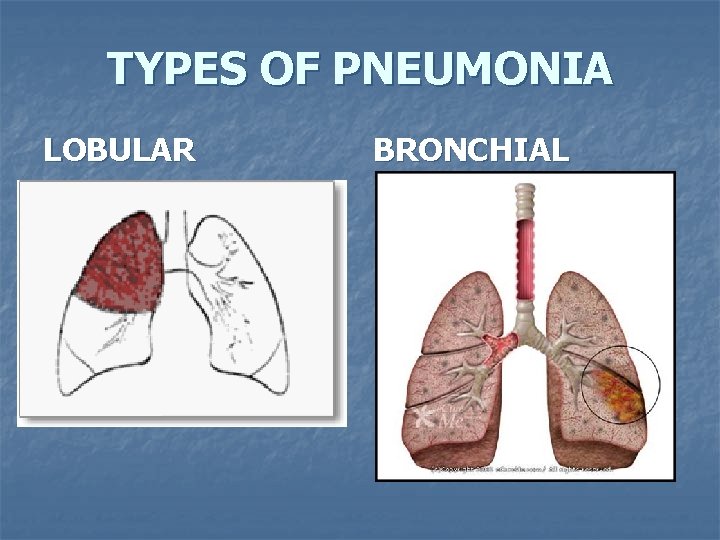

n Lobar pneumonia affects a lobe of the lungs (see x-ray), and bronchial pneumonia can affect patches throughout both lungs. Lobular pneumonia

TYPES OF PNEUMONIA LOBULAR BRONCHIAL